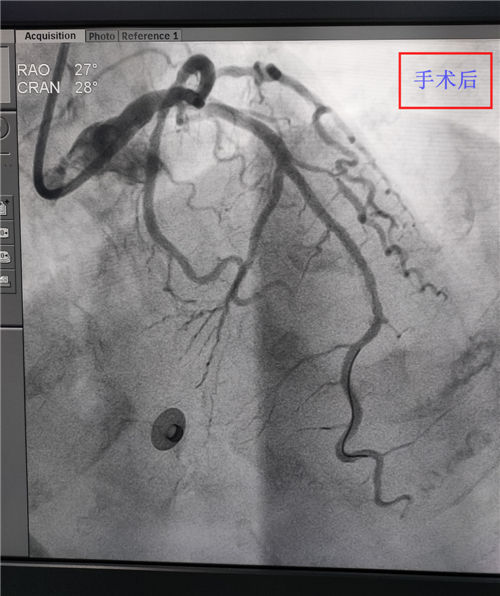

內(nèi)二科成功開展首例急診PCI手術(shù)

? ? ? ?4月19日,我院介入手術(shù)治療團(tuán)隊成功開展了羅江區(qū)首例急診PCI手術(shù)。此次手術(shù),標(biāo)志著我院介入治療技術(shù)更加成熟。

? ? ? ?患者80歲,胸痛2小時于4月19日來我院就診,急診科胸痛中心考慮診斷急性廣泛前壁ST段抬高型心肌梗死,病情危重。經(jīng)與家屬溝通后,我院介入手術(shù)治療團(tuán)隊為患者行急診PCI手術(shù),手術(shù)歷時1個多小時,術(shù)后患者胸痛癥狀明顯改善,恢復(fù)較好。